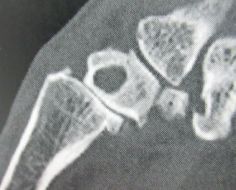

Main - Poignet - Coude Points essentiels de la traumatologie du coude de l’enfant , Christophe Glorion Université Paris Descartes, Sorbonne Paris Cité, Service d’orthopédie infantile, Hôpital Necker Enfants Malades, Paris, France , Stéphanie Pannier Université Paris Descartes – Sorbonne Paris Cité – Service d’orthopédie infantile - Hôpital Necker Enfants Malades - Paris - France / , Z. Péjin Service d’Orthopédie et Traumatologie pédiatrique Hôpital des Enfants Malades, Paris , Alexandra Alves Université Paris Descartes, Sorbonne Paris Cité, Service d’orthopédie infantile - Hôpital Necker Enfants Malades, Paris, France , A. Desroches Service d’Orthopédie et Traumatologie pédiatrique Hôpital des Enfants Malades, Paris , D. Thomas Service d’Orthopédie et Traumatologie pédiatrique Hôpital des Enfants Malades, Paris , Y. Ouchrif Service d’Orthopédie et Traumatologie pédiatrique Hôpital des Enfants Malades, Paris N°268 - Novembre 2017 - Cahier 2 ● 12 min de lecture